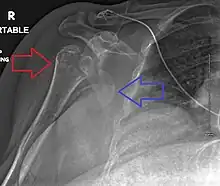

A fracture of the greater tuberosity as seen on AP X ray -

A fracture of the greater tuberosity of the humerus -

Fracture of the greater tuberosity of the humerus -